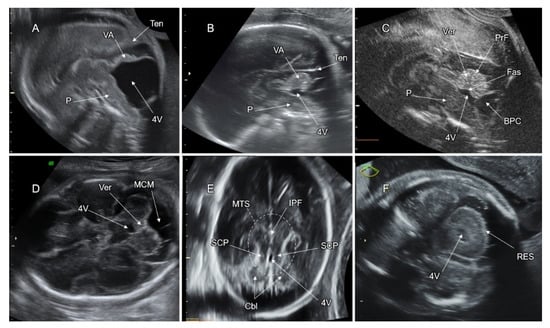

7. Malformations of the Posterior Fossa

7.2. Vermian Agenesis (VA), Hypoplasia (VH), and Dysgenesis (VD)

7.3. Blake’s Pouch Cyst (BPC)

7.4. Mega Cisterna Magna (MCM)

7.5. Joubert Syndrome (JS) and JS-Related Disorders

7.6. Rhombencephalosynapsis (RES)

7.7. PF Anomalies Associated with Tubulinopathies

7.8. PF Anomalies Associated with Cobblestone Malformation (CM)